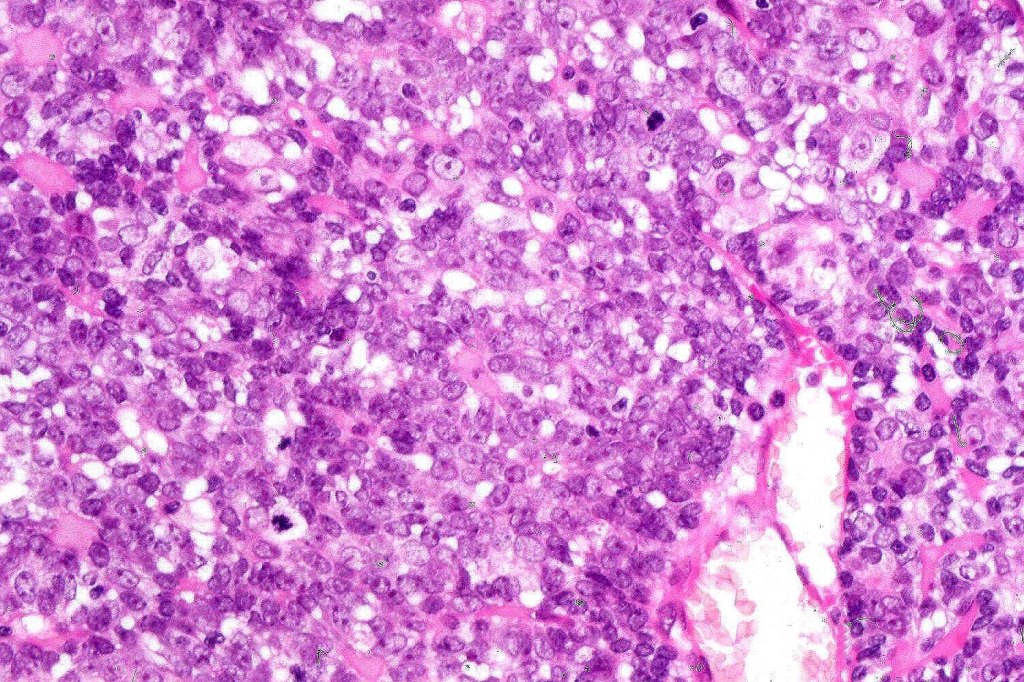

Histological features

•Malignant component shows loss of dual cell population, increased mitotic activity, atypical mitoses & necrosis

•1. Salivary gland type basal cell adenocarcinoma-like pattern, low grade (BCAC-LG)

•2. Salivary gland type basal cell adenocarcinoma-like pattern, high grade (BCAC-HG)

•3. Invasive adenocarcinoma, not otherwise specified (IAC-NOS)